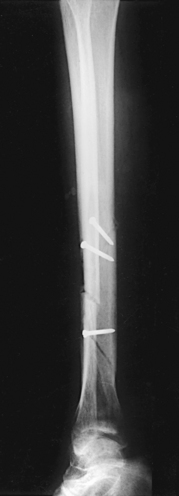

Structures shown: The resulting image shows the tibia, fibula, and adjacent joints (Fig. 6-112).

Fig. 6-112 A, AP tibia and fibula. Long leg length prevented showing entire leg. A separate knee projection had to be performed on this patient. B, Short leg length allowed entire leg to be shown. Spiral fracture of distal tibia with accompanying spiral fracture of proximal fibula (arrows) is seen. This radiograph shows the importance of including the entire length of a long bone in trauma cases. C, AP tibia and fibula on a 4-year-old with neurofibromatosis.